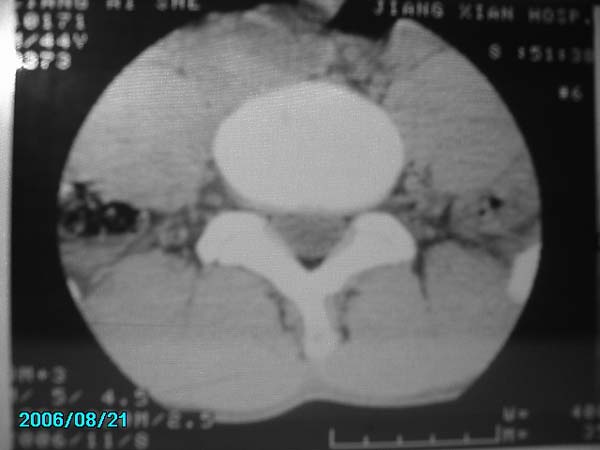

男,40岁,腰疼半年

腰4-5椎间盘后缘变平直,可考虑椎间盘轻度突出。余未见异常。

l4/5椎间盘膨出。

腰4-5椎间盘轻度突出。余未见异常。

腰4-5、腰5-骶1椎间盘后缘变平直,可考虑椎间盘轻度突出。余未见异常

除有第3-5腰椎椎体后缘中央血管沟显示外,诸椎间盘比较正常。我也象13081830109战友那样看见了指纹,呵呵。

部分层面有轻度彭出。